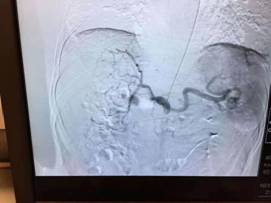

如何解决肝癌介入术后的这个“老大难”问题也成为介入团队的攻关目标之一。团队通过反复查阅文献和与国内外同行的广泛交流学习,发现通过手部的桡动脉穿刺,即可有效解决左某的顾虑。但该途径的穿刺血管很细,穿刺成功率低;最难的地方还在于这种治疗路径与传统治疗路径完全相反,对医生的操作技巧要求极高。患者利益至上是二院肝胆外科人的首要目标。介入团队医生们将该手术难点逐点分解攻破,并反复演练,终于掌握了这一方法。10月31日,由游科医生主刀,幸运的左某成为该技术的第一位获益者。一个半小时后,左某自己走下手术床,然后步行回到肝胆外科病房,于11月1日出院回家。

众所周知,肝动脉化疗栓塞术(TACE术)是肝癌治疗的有效、微创手段。其操作原理将导管选择性或超选择性插入到肝脏肿瘤供血靶动脉后,注入适量的栓塞剂,使靶动脉闭塞,从而“饿死”肝肿瘤细胞。手术过程中,医生们通过采用注入抗癌药物或药物联合微粒、微球等方式起化疗性栓塞作用,最终达到“杀死”现有肿瘤的效果。

桡动脉入路相较于股动脉入路的优点

1.不需要患者腿部的制动

2.避免患者卧床8小时身不能翻,做完手术后病人依然行动自如

3.极大的提高了手术患者的就医质量和体验

4.缩短了患者的住院时间,节省了费用

5.据文献报道,桡动脉入路较股动脉入路,并发症更少